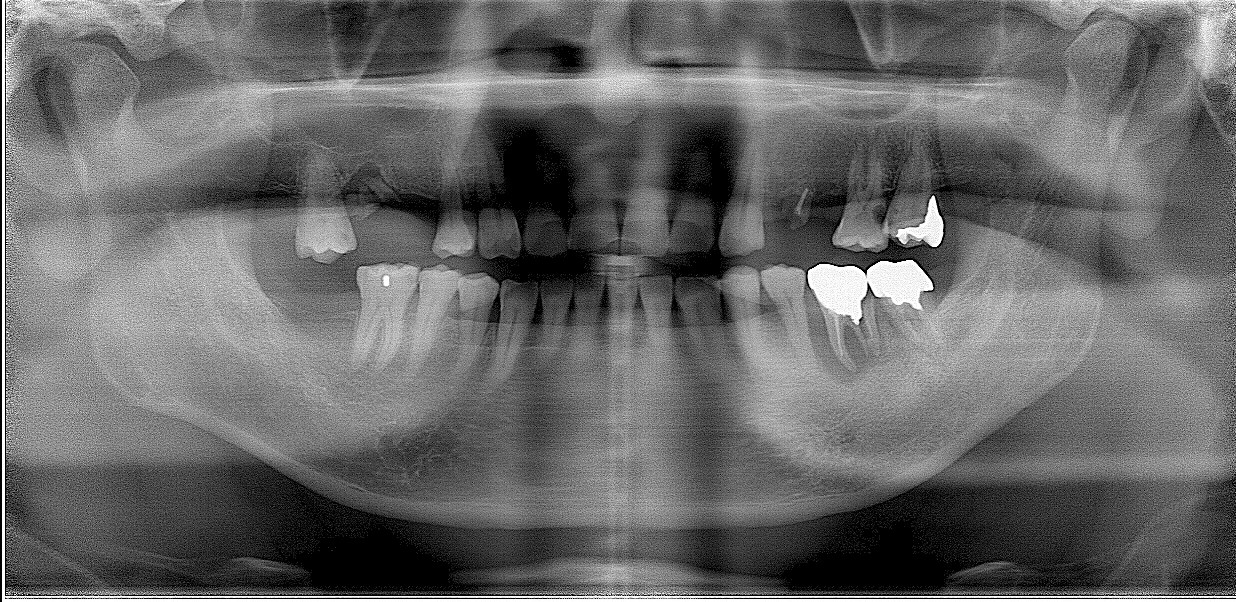

パノラマになります

奥歯が欠損にて確かに噛みにくい状況となっていました

左上6番は動揺もかなりあるために根管治療を行い最終的にインプラントと固定を行っていく計画としました